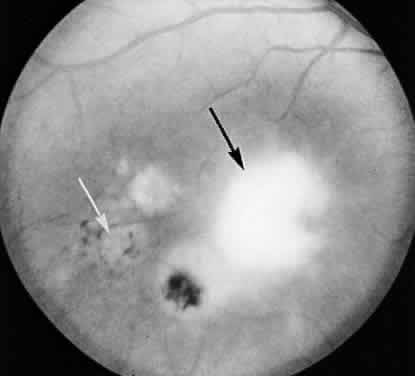

Toxoplasma gondii has a primitive type of mouth referred to as a conoid. This organelle is extended as the parasite “searches” for a host-cell and makes contact with the plasmalemma of a potential host cell immediately before entry. The work of Nichols and associates58 shows that rhoptries, other specialized organelles that are thought to contain lytic enzymes, protrude anteriorly into the conoid and fuse with the limiting membrane of the conoid just before the entry of the parasite into a host cell. Discontinuities develop in this membrane, through which the contents of the rhoptries appear to be discharged. After discharge, the rhoptries resemble empty sacs (Fig. 4). At the site where the conoid indents the host cell, phospholipid vesicles are formed in the plasmalemma of the host cell and a small discontinuity can be seen to develop in this membrane.34 The parasite then squeezes through this opening until it is totally enveloped within the cytoplasm of the host cell. The site of perforation subsequently shows a healing over or restoration of the continuity of the plasmalemma. The conoid of the parasite then retracts to its normal resting position.

Fig. 4. A longitudinal section through a T gondii organism that has recently invaded a host cell. The inset at higher magnification illustrates ribosomes (r*) attached to the endoplasmic reticulum (white arrow). (× 28,400; inset × 81,000.) n, nucleaus; Gc, Golgi's complex; m, mitochondrion; er, endoplasmic reticulum; c, conoid; r, rhoptry; rs, rhoptry sac.